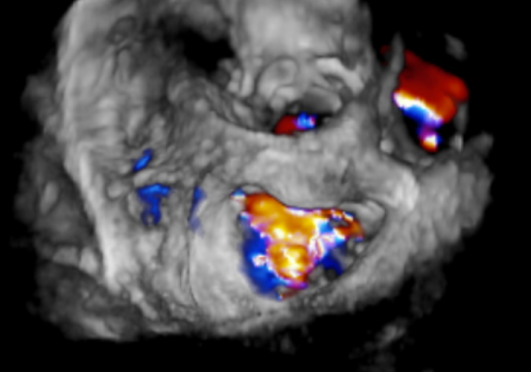

手术于全麻下进行,术前TEE提示重度功能性二尖瓣反流,反流位于A2/P2,瓣膜活动度可(图1)。手术采用经典股静脉房间隔途径,房间隔穿刺后置入24F导引导管及二尖瓣夹输送系统,在TEE引导下准确植入一枚二尖瓣夹,瓣膜夹位置稳定,植入后反流基本消失(图2),二尖瓣跨瓣平均压力阶差2mmHg,双孔化形成,遂移除器械输送系统。患者术后恢复良好,瓣膜夹位置稳定,拟于近期出院。

图2:术后TEE提示,二尖瓣夹植入后反流基本消失,双孔化形成